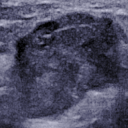

Lesion patches from different modalities can be utilized for classification in different manners. Unfortunately, image registration is almost impossible because of the difference in mammography and ultrasound imaging techniques. Moreover, even ultrasound images of the same lesion are highly different, as the images are captured in various views and the breast is easily deformed by the mechanical pressure applied by the transducer (see Figure 5).

Refer to caption

Figure 5: Same lesion captured in different views in ultrasound screening.